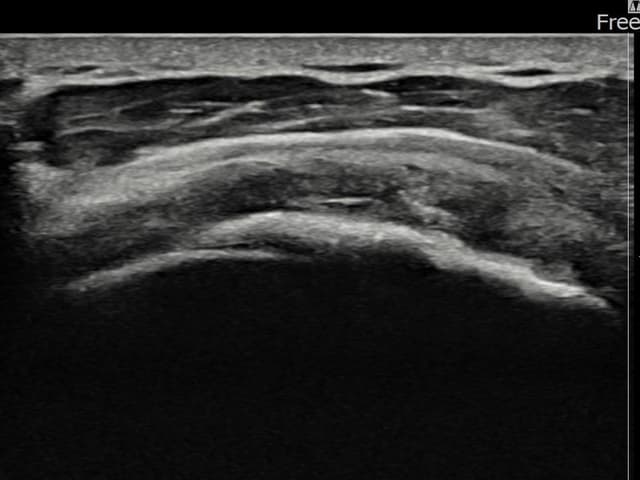

[촬영시기:25.08.20~25.11.18]

[어깨인대 축소봉합술] 좌측 어깨 광범위 파열로 팔 들어올리기가 매우 어려웠습니다.